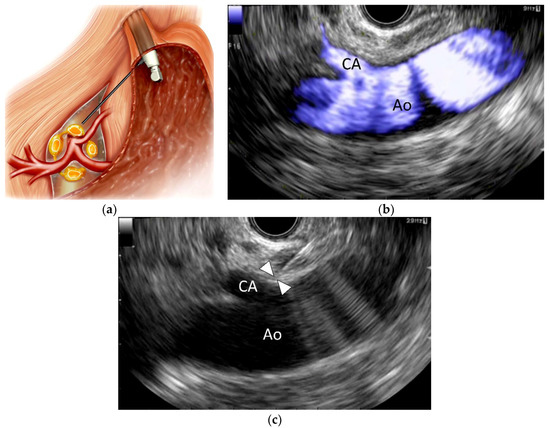

EUS-CPN, first described in 1996 by Wiersema and Wiersema [8], is a relatively new technique in which a local anesthetic (bupivacaine or lidocaine) and a neurolytic agent (absolute alcohol or phenol) are injected around the CP under EUS guidance (Figure 1). EUS-CPN can be performed with either an oblique-viewing or forward-viewing curved linear-array echo endoscope [8,23,24]. Under moderate sedation, the echo endoscope is passed per-orally into the esophagus. Under endoscopic visualization, the echo endoscope is advanced through the gastroesophageal junction into the stomach. EUS imaging from the posterior lesser curvature of the gastric body allows visualization of the longitudinal view of the aorta. The aorta is traced distally to the origin of the CA, which is the first major branch below the diaphragm. The CP per se cannot be identified as a clear structure but is located based on its position around the celiac trunk. A 19- or 22-gauge aspiration needle filled with normal saline solution is prepared, passed through the biopsy channel and affixed to the hub. If a specially designed 20-gauge “spray needle” with multiple side holes is available [63], it could be used to spread the desired agent across a larger area.

EUS-CPN can be performed via a unilateral approach or a bilateral approach [19,56]. In the unilateral approach, the neurolytic agent is injected adjacent to a point just above the celiac trunk; in the bilateral approach, the agent is injected on both sides of the celiac trunk. For the unilateral approach, the needle is inserted under EUS guidance adjacent to the CA origin. To avoid transient pain induced by chemical stimulation with a neurolytic agent, 2–3 mL of a local anesthetic (bupivacaine or lidocaine) is initially injected. Then, a mixed solution of absolute alcohol and contrast medium is injected around the celiac trunk. The total volume of alcohol injected is usually 10–20 mL in EUS-CPN. For the bilateral approach, the probe is rotated clockwise toward the patient’s left at the level of the CA until the celiac trunk is no longer visualized but the aorta is still visible. The agent is injected in this region. Subsequently, the same process is carried out on the opposite side of the aorta (with counter-clockwise rotation).

Figure 1. Endoscopic ultrasound-guided celiac plexus neurolysis (EUS-CPN). (a) Schematic of EUS-CPN; (b) Color flow EUS image from the lesser curvature of the stomach showing a longitudinal view of the aorta (Ao) and celiac artery (CA); (c) EUS image of EUS-CPN during needle puncture. A 22-gauge needle was advanced adjacent to the CA origin. Arrowheads indicate the needle tip. Blue: vascular flow.